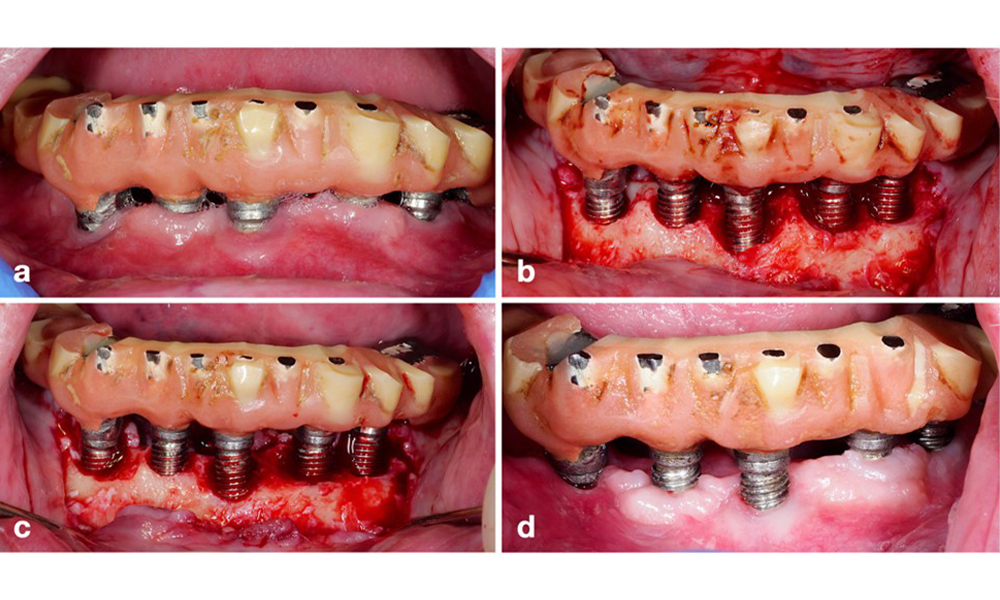

The World Workshop on the Classification of Periodontal and Peri‐Implant Diseases and Conditions from 2017 established diagnostic criteria for peri-implant mucositis and peri-implantitis (Renvert et al. 2018). Peri-implant mucositis is defined as (1) presence of inflammation around the implant (i.e., redness, swelling, line or drop of bleeding within 30 seconds of probing), combined with (2) no additional bone loss after initial healing (figure 1).

Implant in position 26 with peri-implant mucositis (a–c). The probing depth value of 5 mm (b) remains consistent with the measurement taken a few weeks after placing the prosthetic reconstruction. There is bleeding on probing (c) but the radiograph indicates no additional bone loss beyond what is expected for marginal bone remodelling (d).

Figure 1. Implant in position 26 with peri-implant mucositis (a–c). The probing depth value of 5 mm (b) remains consistent with the measurement taken a few weeks after placing the prosthetic reconstruction. There is bleeding on probing (c) but the radiograph indicates no additional bone loss beyond what is expected for marginal bone remodelling (d).